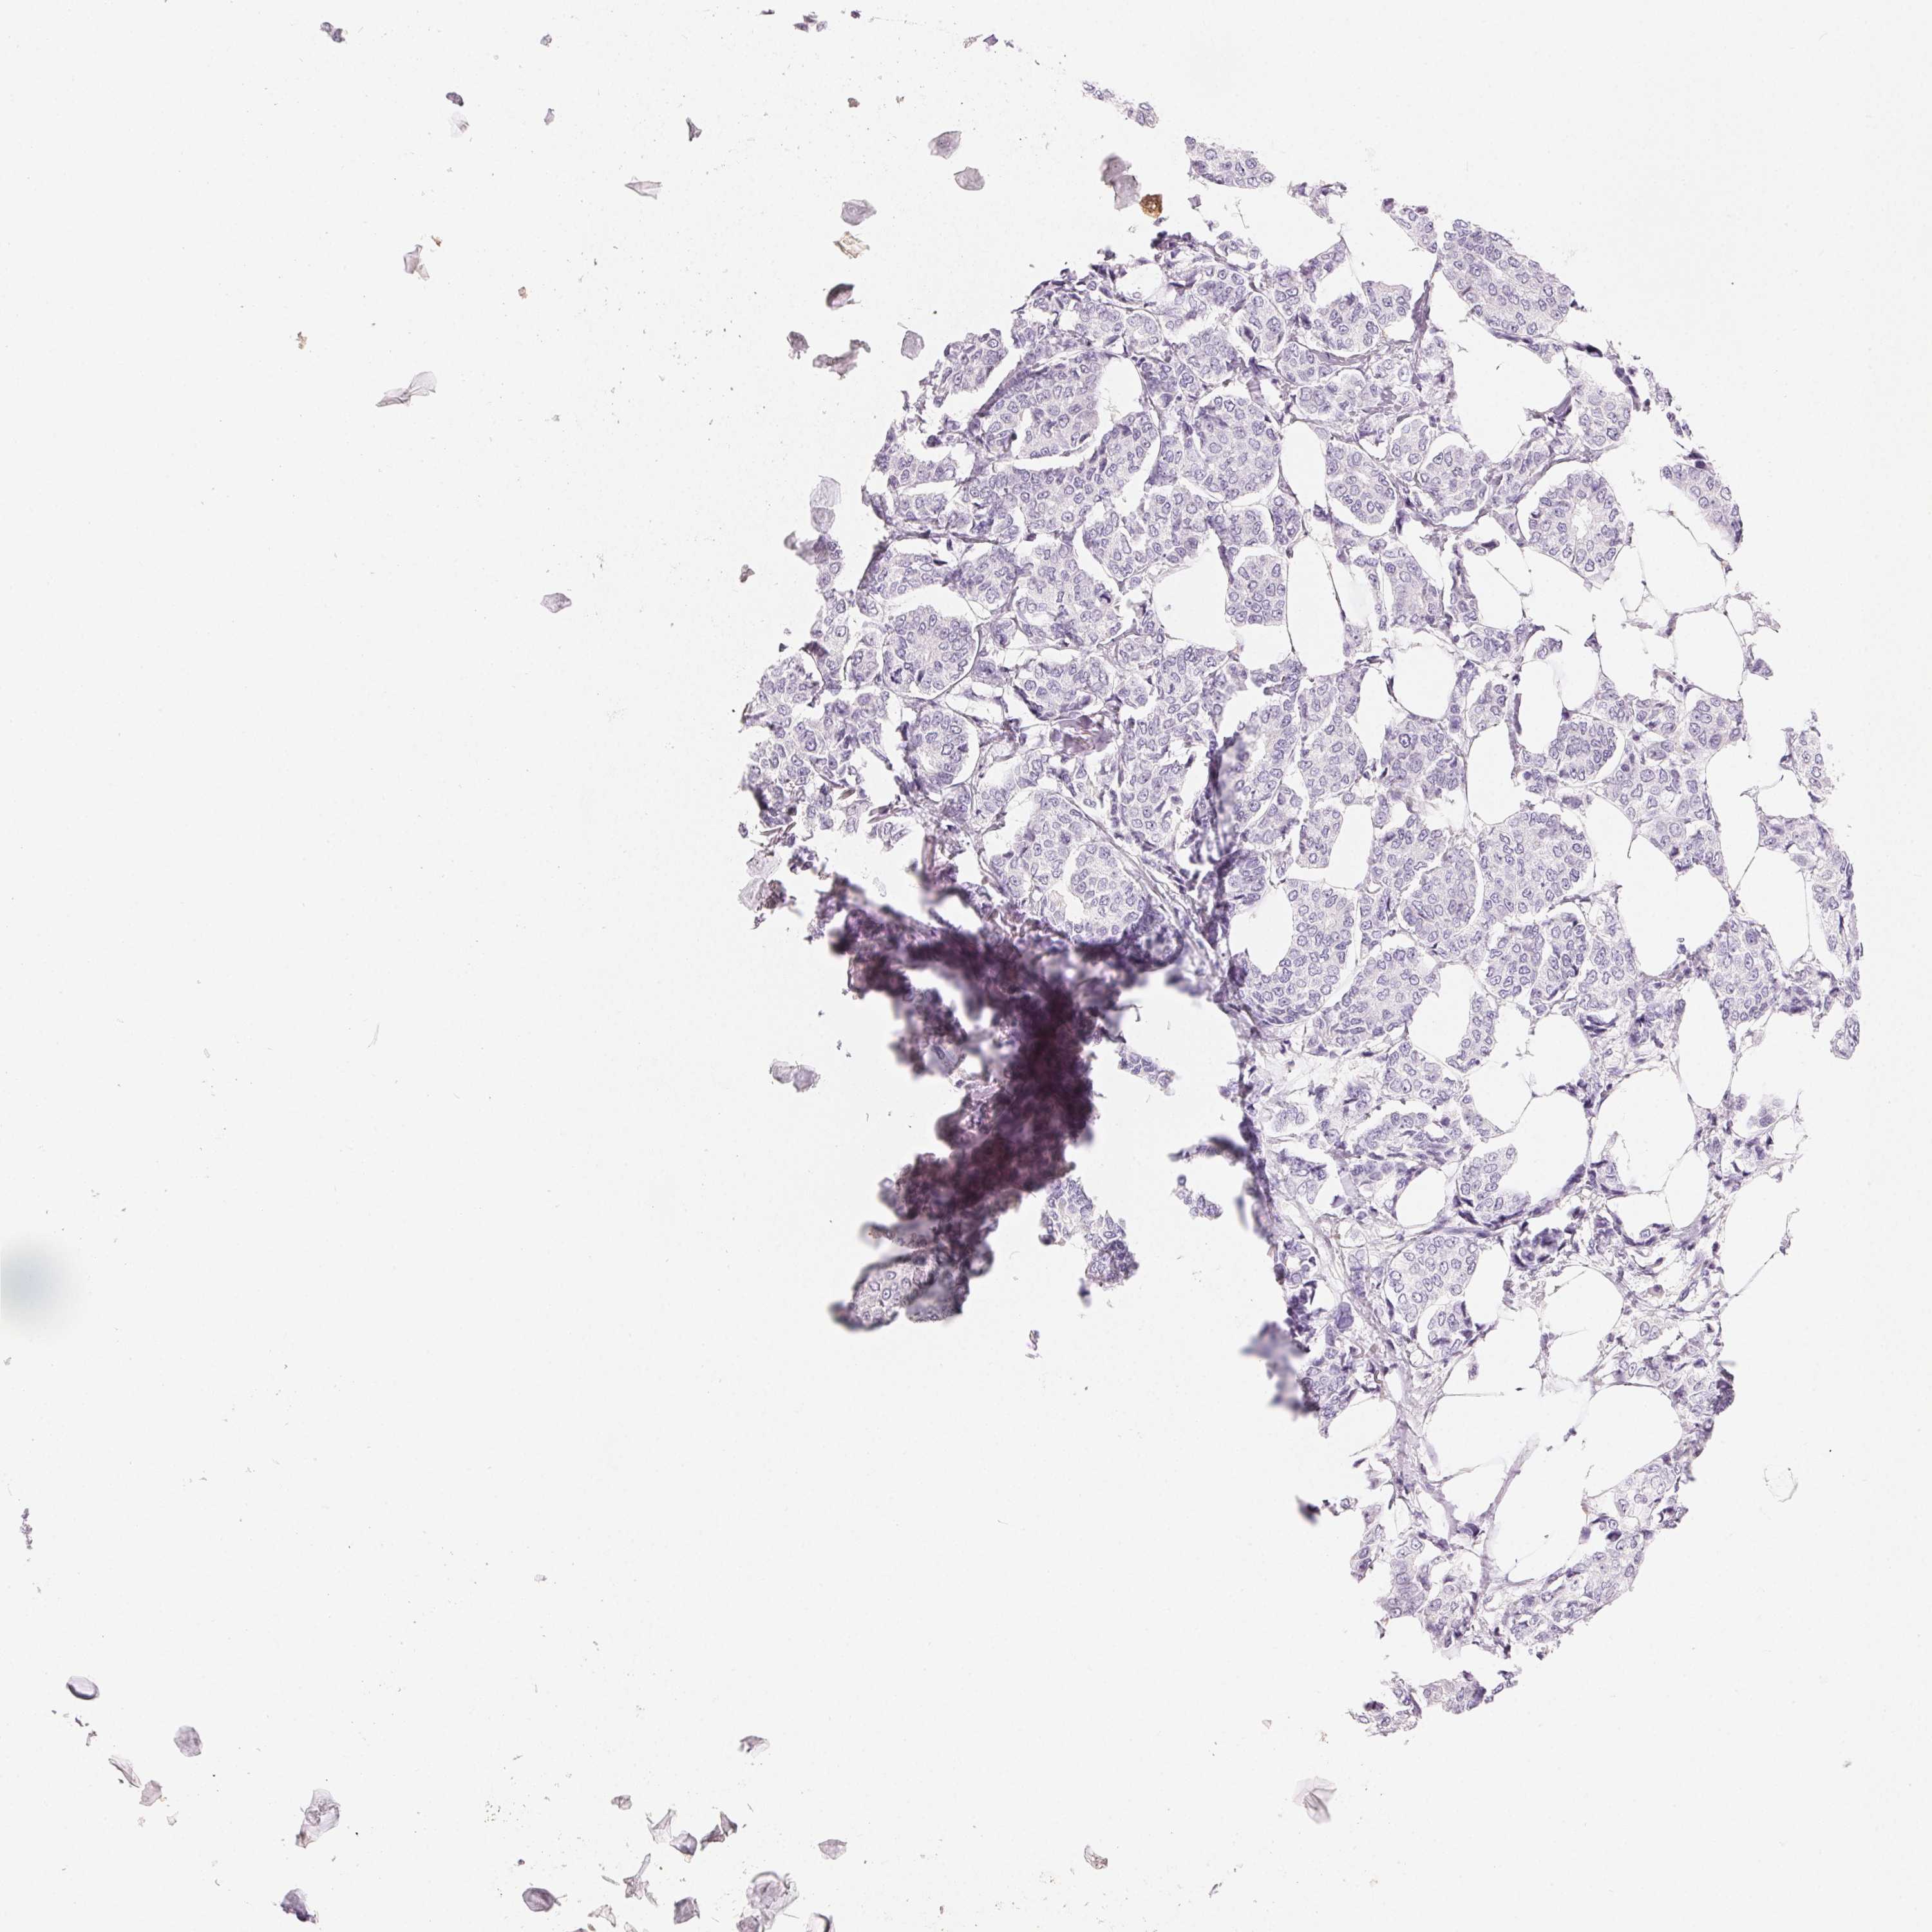

CANCER BREAST CANCER Show tissue menu

BRCA TCGA BRCA VALIDATION PROTEIN EXPRESSION